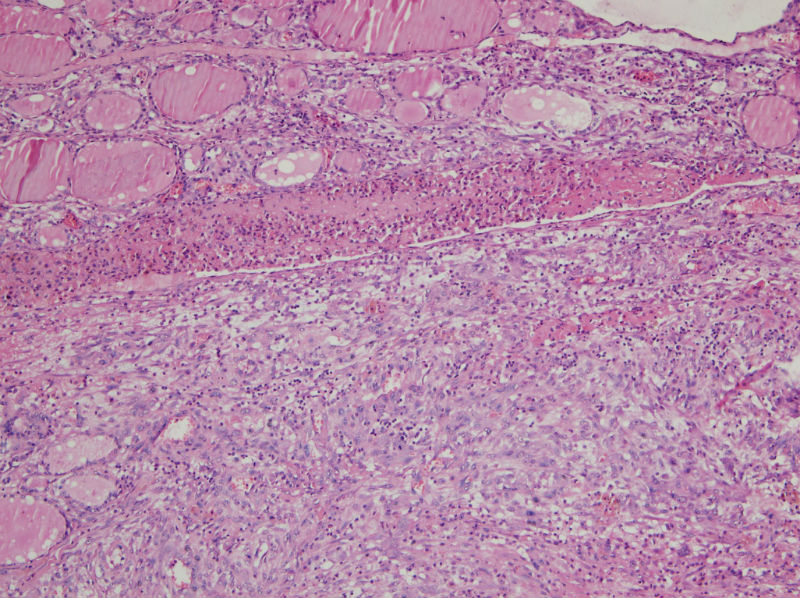

男,44,甲状腺囊肿.直径1.5公分,内流清亮液

补充,,包膜不完整..囊内壁就是图2,图3..

结节性甲状腺肿伴囊性变。图2右上角的滤泡上皮似乎有些嗜酸性变。总之:良性病变。图13伴有出血。

结节性甲状腺肿伴囊性变     还可见囊壁周围伴有感染吧。

该囊肿不与舌骨相连,不是甲状舌骨囊肿。上皮下淋巴细胞不丰富,不是腮裂囊肿。

结节性甲状腺肿伴出血、囊性变。囊肿边上的滤泡大小不一,纤维组织增生,还可见炎细胞浸润。

结节性甲状腺肿囊性变伴周围慢性炎细胞感染。

结节性甲状腺肿伴出血、囊性变。